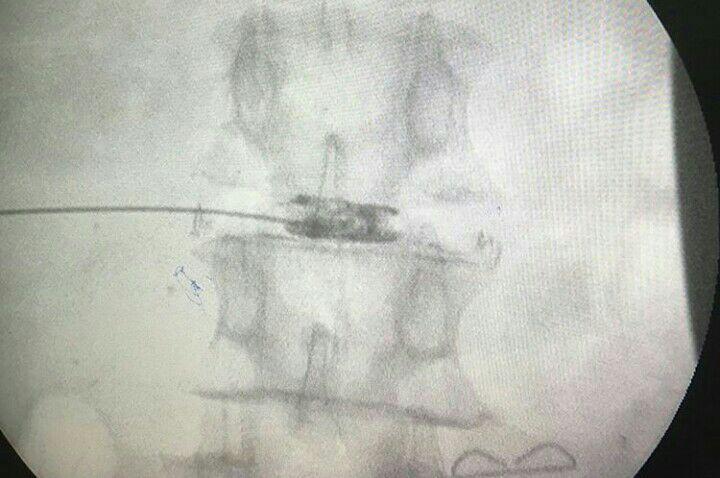

-لیزر(جراحی بسته) دیسک کمری

-اوزون تراپی دیسک بین مهره ای

-درمان تنگی کانال نخاعی غیرقابل جراحی

استفاده از روشهایی مانند تزریقات تخصصی (مانند اپیدورال، بلوک عصبی)، طب سوزنی، فیزیوتراپی، تحریک الکتریکی عصب و روشهای کم تهاجمی جراحی.